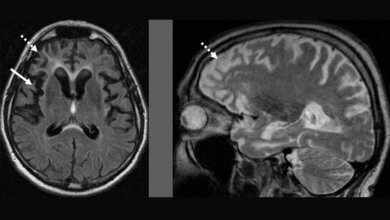

Mithilfe dieses Modells konnten die Wissenschaftler eine toxische Anhäufung des Proteins NPTX2 als Bindeglied zwischen dem Fehlverhalten von TDP-43 und dem Absterben der Nervenzellen nachweisen. Um ihre Hypothese zu überprüfen, untersuchten sie das Hirngewebe von verstorbenen ALS- und FTD-Patientinnen und -Patienten. Tatsächlich stellten sie fest, dass sich NPTX2 auch hier in Zellen anreichert, die eine abnorme Anhäufung von TDP-43 enthalten. Das iNets-Zellkulturmodell konnte die Pathologie von ALS- und FTD-Betroffenen also genau vorhersagen.